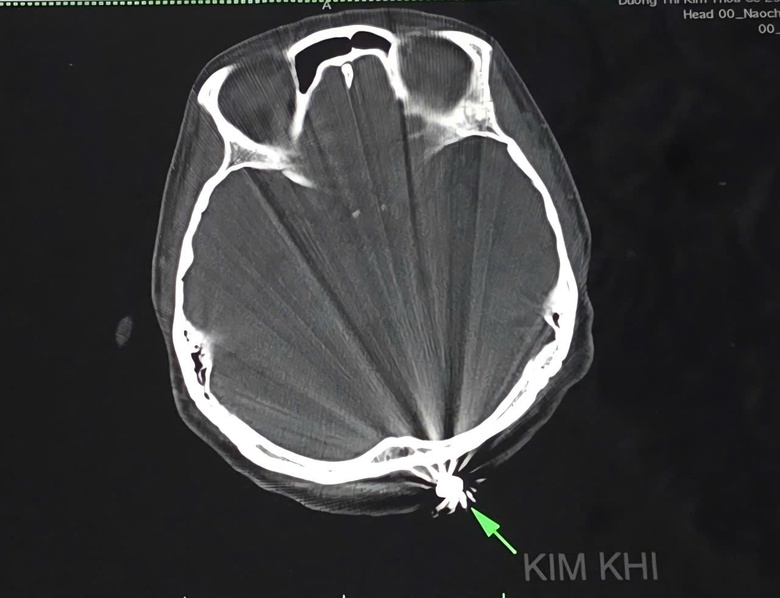

Phim chụp vùng đầu nữ bệnh nhân D.T.K.T với viên đạn ghim vào vùng chẩm (phía sau đầu - ngay trên gáy).

Bệnh nhân nữ D.T.K.T (40 tuổi, ngụ tại TP Cần Thơ). Theo thông tin từ gia đình, trước đó, khi đang làm tại vườn nhà, bà D.T.K.T bất ngờ bị một vật cứng dạng bi tròn bay đến găm vào vùng chẩm (phía sau đầu - ngay trên gáy), gây chảy máu nhiều.

Nạn nhân hoảng hốt gọi người nhà hỗ trợ và được đưa đến khoa Cấp cứu của Bệnh viện Đa khoa Trung ương Cần Thơ lúc 18h41 cùng ngày trong tình trạng đau đầu, vết thương vùng chẩm khoảng 1cm đã cầm máu. Bên cạnh vết thương có một khối cứng hình tròn, kích thước khoảng 0,5 x 0,5cm.